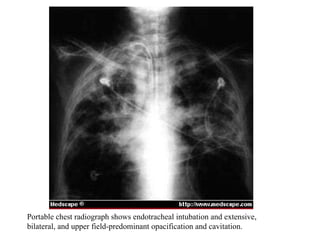

Portable chest radiograph shows endotracheal intubation and extensive,  bilateral, and upper field-predominant opacification and cavitation.